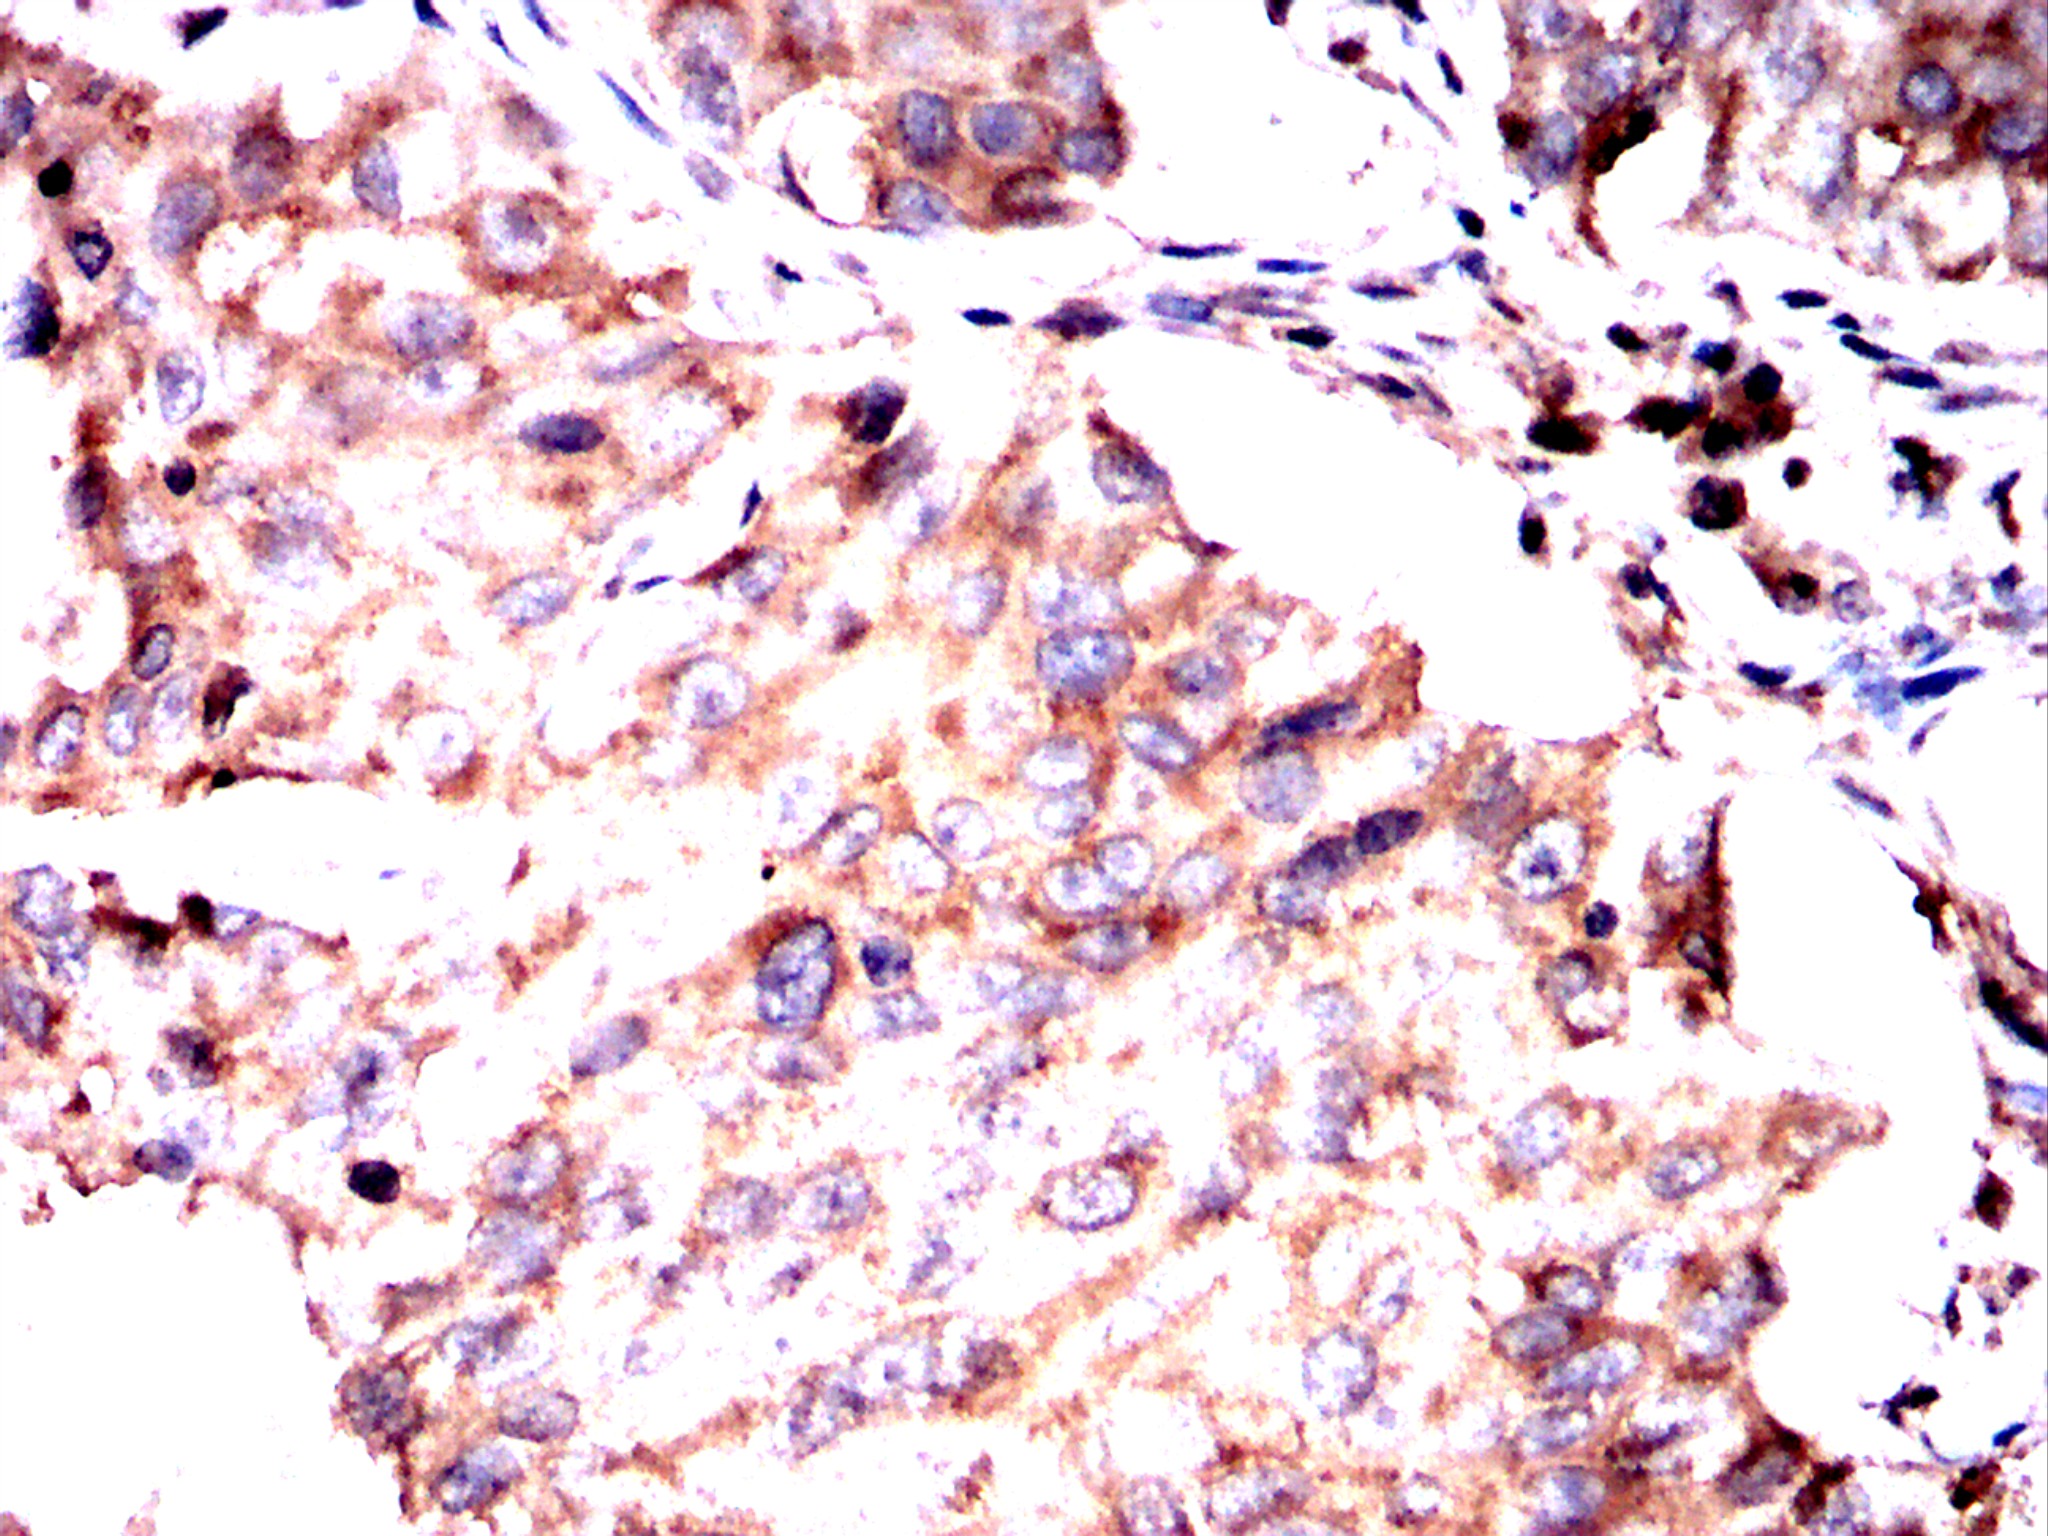

Immunohistochemical analysis of paraffin-embedded breast cancer tissues using PSMB8 antibody with DAB staining. Pre-treat the sections with heat-mediated antigen retrieval using sodium citrate buffer (pH 6.0) (OM750020) for 2 minutes. Wash the sections with ddH₂O and PBS (OM750003). Block the tissue with 10% non-immune goat serum(OM760028) at room temperature for 30 minutes. Incubate the tissue with the primary antibody diluted at a ratio of 1:1500 at 4°C overnight. At room temperature, dilute the secondary antibody, Goat Anti-Rabbit IgG(H&L)-HRP (OM643487), at a ratio of 1:200 and incubate for one hour. Use DAB(OM760029)as the chromogenic agent. Counterstain the tissue with hematoxylin, and mount the tissue sections with neutral gum.WB

Immunohistochemical analysis of paraffin-embedded breast cancer tissues using PSMB8 antibody with DAB staining. Pre-treat the sections with heat-mediated antigen retrieval using sodium citrate buffer (pH 6.0) (OM750020) for 2 minutes. Wash the sections with ddH₂O and PBS (OM750003). Block the tissue with 10% non-immune goat serum(OM760028) at room temperature for 30 minutes. Incubate the tissue with the primary antibody diluted at a ratio of 1:1500 at 4°C overnight. At room temperature, dilute the secondary antibody, Goat Anti-Rabbit IgG(H&L)-HRP (OM643487), at a ratio of 1:200 and incubate for one hour. Use DAB(OM760029)as the chromogenic agent. Counterstain the tissue with hematoxylin, and mount the tissue sections with neutral gum.